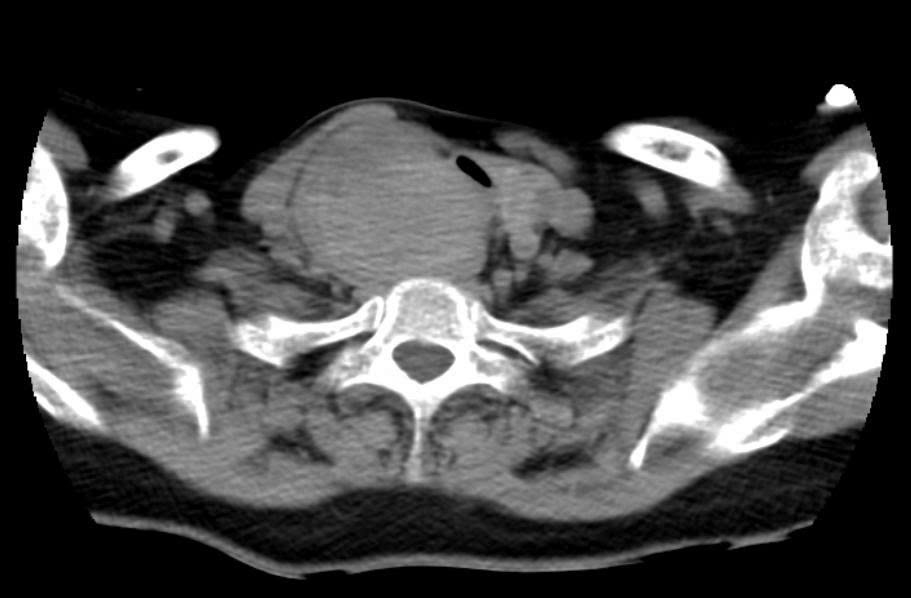

Khối u chèn ép khí quản và thực quản |

Sau khi được chuyển từ Bệnh viện Tim Hà Nội, các bác sĩ Bệnh viện Ung Bướu Hà Nội xác định bệnh nhân có khối u thùy phải tuyến giáp kích thước 6x8cm, nằm kẹt giữa thực quản và khí quản. Khối u này đã chèn ép khí quản đến mức đường thở chỉ còn khoảng 2mm trên đoạn dài 20mm, gây biến dạng giải phẫu nghiêm trọng. Khí quản của bệnh nhân còn bị đẩy lệch trái 2cm, xẹp và dễ co thắt, khiến việc tiếp cận phẫu thuật vô cùng khó khăn. Đặc biệt, khối u tăng sinh mạch rất mạnh, tiềm ẩn nguy cơ chảy máu cao trong và sau mổ.